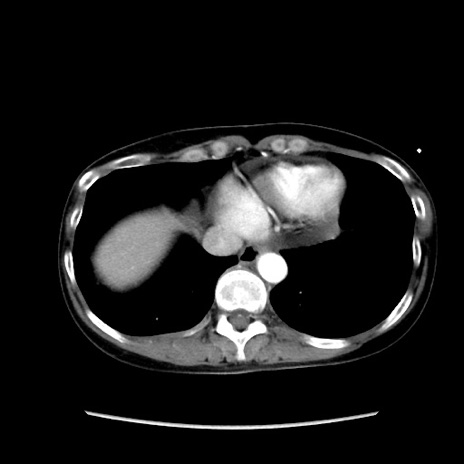

症例32(横断像)

【症例】40歳代 女性

【主訴】上腹部痛、嘔気・嘔吐

【現病歴】約9時間前頃から急に上腹部痛、嘔気、嘔吐が出現。改善しないため救急要請。

【既往歴】子宮頚癌(広汎子宮全摘術、放射線療法)、腸閉塞

【身体所見】腹部:平坦、軟、腸雑音亢進、上腹部を中心に腹部全体に圧痛あり。

【データ】WBC 8400、CRP 0.03